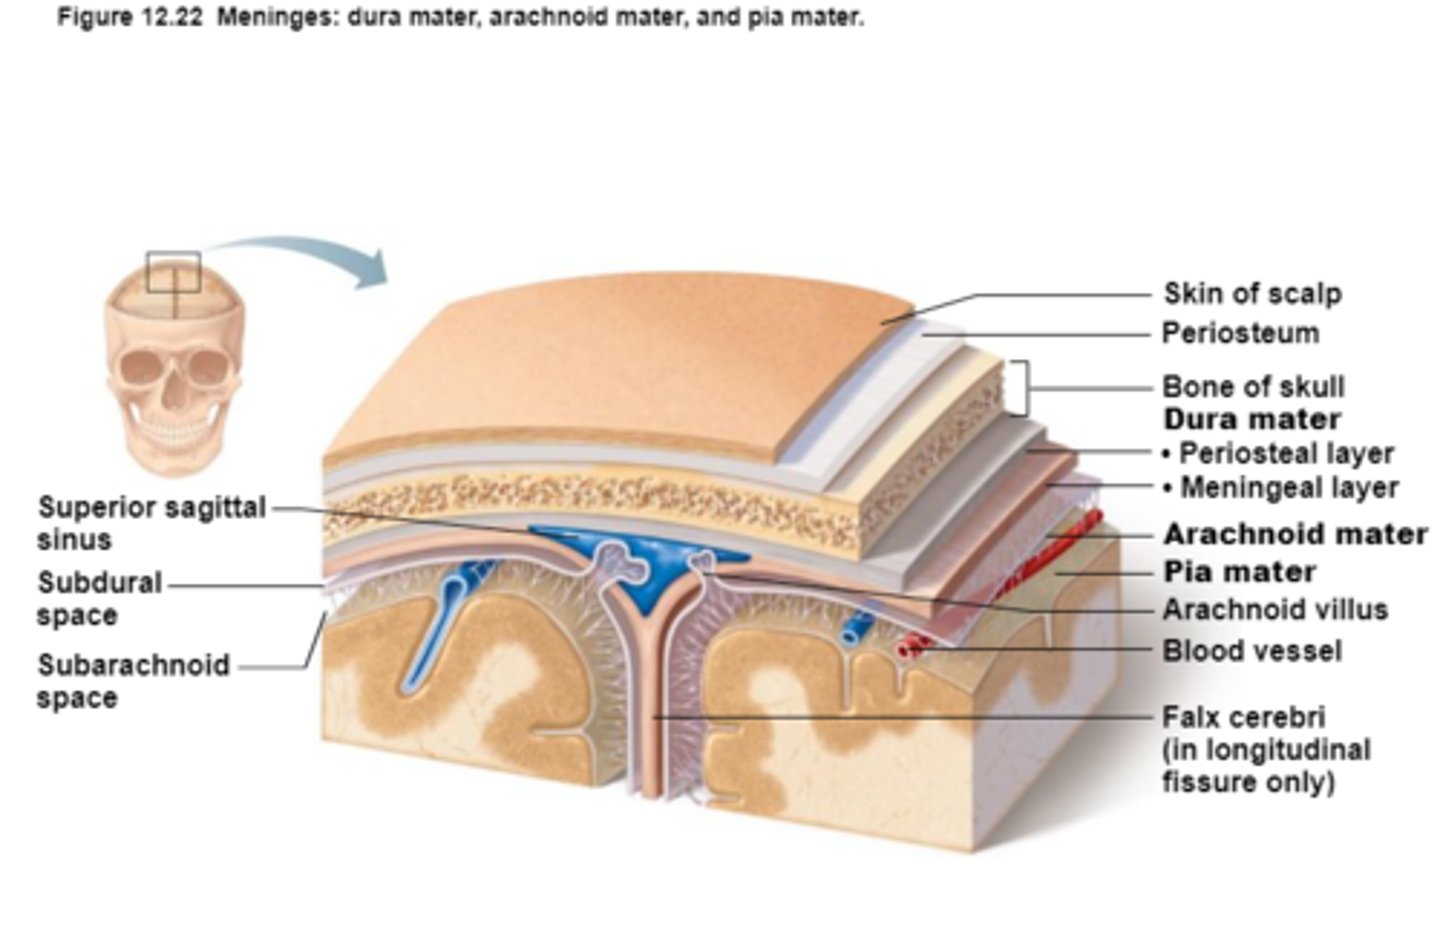

Protection of the CNS

1) scalp and skin

2) skull and vertebral column

3) meninges

Meninges

Connective tissue membranes that lie just external to the CNS organs that:

-Cover and protect the CNS

-Protect blood vessels and enclose venous sinuses

-Contain cerebrospinal fluid

3 Layers (external to internal) of Meninges

Dura Mater,

Arachnoid Mater,

Pia Mater

Dura Mater

First layer of Meninges,

Has layers that can separate to form dural sinuses:

-Periosteum

-Meningeal layer

Arachnoid Mater

Second layer of the Meninges,

Subarachnoid space with cerebrospinal fluid

Pia Mater

Third layer of Meninges